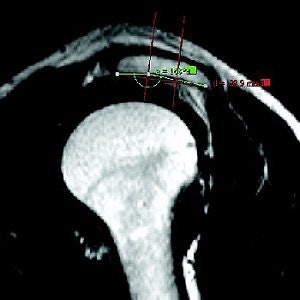

![]() ![]() ![]() |

| A 63-year-old man with impingement syndrome of shoulder. Whereas outlet view radiograph (top) depicts curved acromion (type 2), MR image (middle) in position S-1 reveals blunt acromial hook (type 3), which is also confirmed by 3D model (above) and intraoperatively. Mayerhoefer ME, Breitenseher MJ, Roposch A, Treitl C, Wurnig C, "Comparison of MRI and Conventional Radiography for Assessment of Acromial Shape" (AJR 2005; 184:671-675). |